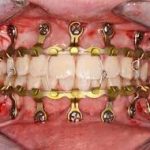

Maxillomandibular fixation

A temporary fixed connection of the maxillary and mandibular teeth, typically with wire, for use in treating a mandible fracture.